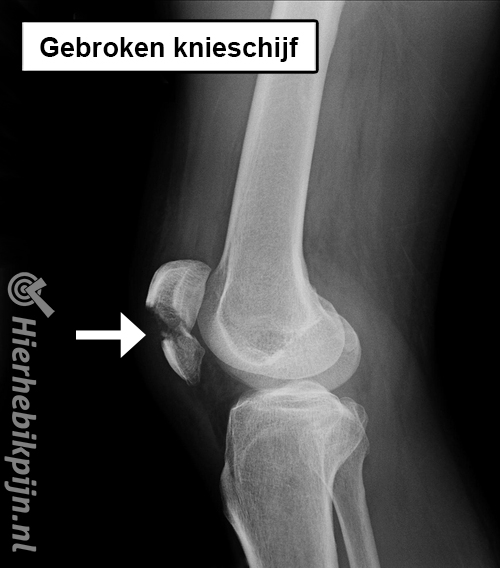

- page_id_307_title

page_id_307_title

page_id_307_lead

page_id_307_body